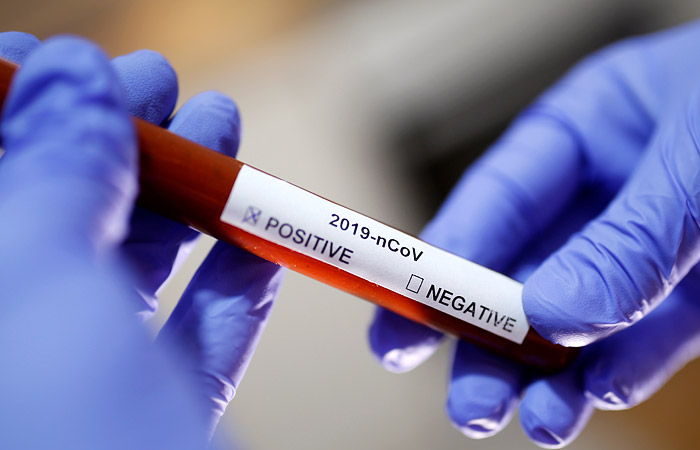

МОЗ: Уперше з початку пандемії було зроблено понад 100 тисяч ПЛР-досліджень за добу

Депутати Вараської міської ради виділили майже 2 мільйони для придбання тест-систем